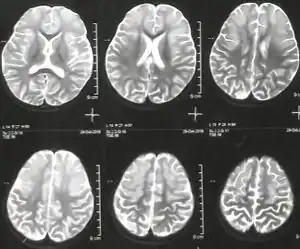

Argininemia is an autosomal recessive urea cycle disorder where a deficiency of the enzyme arginase causes a buildup of arginine and ammonia in the blood. Ammonia, which is formed when proteins are broken down in the body, is toxic if levels become too high; the nervous system is especially sensitive to the effects of excess ammonia.[2][6]

Signs and symptoms

The presentation of argininemia, in those that are affected, is consistent with the following:[2][3]

- Lethargy

- Dehydration

- Hypotonia

- Growth is stunted

- Microcephaly

- Seizures